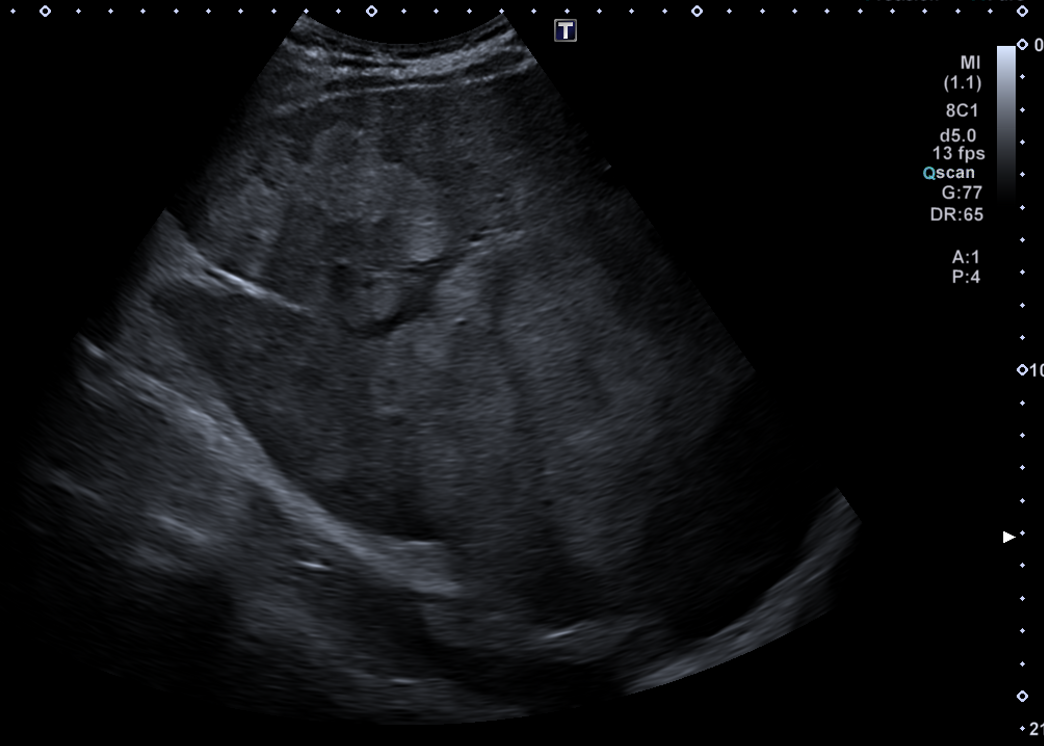

Descripción de los hallazgos ecográficos y las imágenes más relevantes para la resolución del caso

En ecografía en Centro de Salud: La práctica totalidad del parénquima hepático se encuentra sustituida por múltiples lesiones sólidas nodulares hiperecoicas, de predominio en el lóbulo hepático derecho, donde presentan tendencia a la confluencia y conforman una masa que alcanza los 13 cm de diámetro máximo. La vena porta es permeable y ectásica, con esplenomegalia. Ambos son signos de hipertensión portal.

Ante estos hallazgos se deriva al paciente a Urgencias.